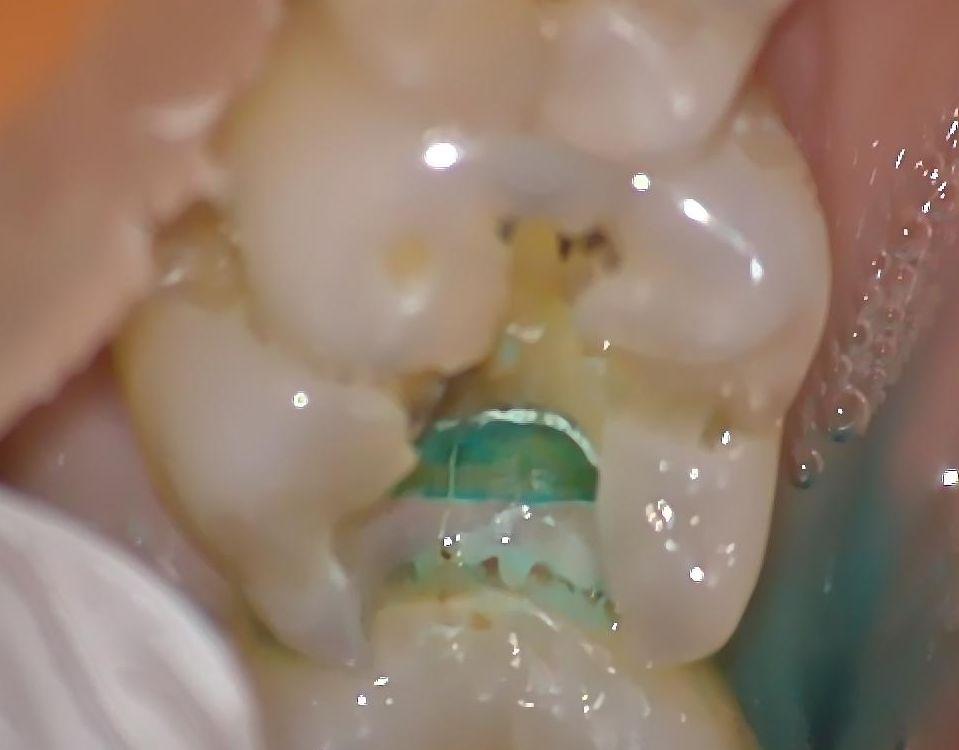

青く虫歯を染め出す薬で見てみると虫歯が残った状態を確認できます。

う蝕検知液を使い虫歯の染め出しを行い